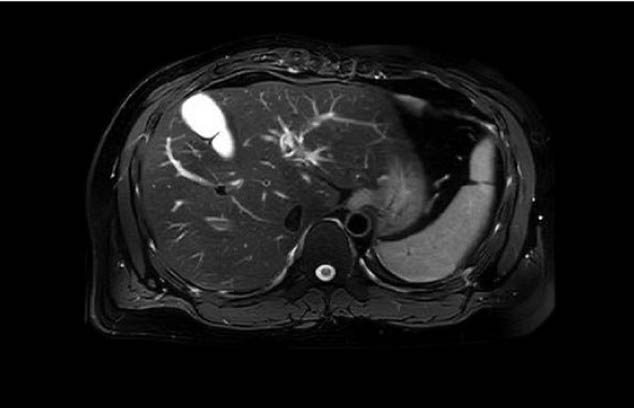

EXCEPTIONAL IMAGE QUALITY

- Best-in-class homogeneity and gradient performance

- World’s largest field of view (60x60x50 cm)

- Motion insensitive sequences for clearer images